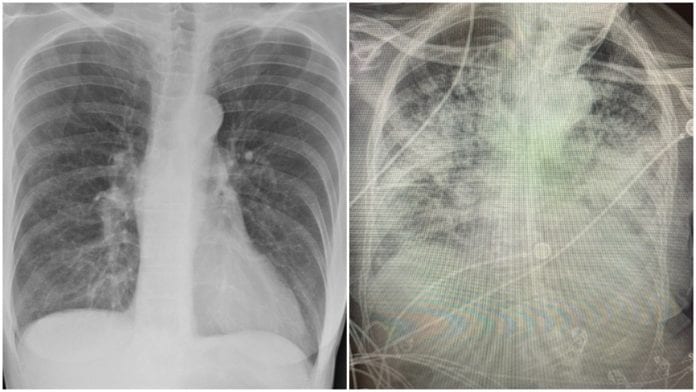

La cirujana estadounidense Brittany Bankhead-Kendall, profesora asistente de la Universidad Técnica de Texas comparó radiografías de los pulmones de pacientes normales, con Covid-19 y de fumadores: el resultado es alarmante.

“Los pulmones post-covid se ven peor que cualquier tipo de pulmón de fumador que hayamos visto. Y colapsan. Y se coagulan. Y la falta de aire persiste y no para”, señaló la especialista.

De acuerdo con los investigadores, los pulmones de un paciente sano deberían verse limpios y con mucho espacio negro, que es básicamente aire, mientras un pulmón de un fumador tiene líneas blancas, como una especie de neblina, aspecto que indica cicatrización y congestión. Pero en el caso de pacientes post Covid, muestran pulmones que parecen estar casi completamente blancos, en otras palabras, severamente dañados. “Incluso si no sientes problemas ahora, el hecho de que eso esté en la radiografía de tu tórax es un indicativo de que posiblemente tengas problemas más adelante”, explicó la cirujana Bankhead-Kendall. Asimismo la especialista señala que es necesario mantener todas las medidas necesarias para evitar contagios, ya que las consecuencias en el cuerpo pueden ser irreversibles, aún para los asintomáticos. “No es algo que puedas ignorar. Esto no es algo que quieras tener. Porque incluso si sobrevives, es posible que te quedes con algunas complicaciones graves que te hagan muy difícil volver a tu funcionamiento inicial”, finalizó.¿Qué te pareció?